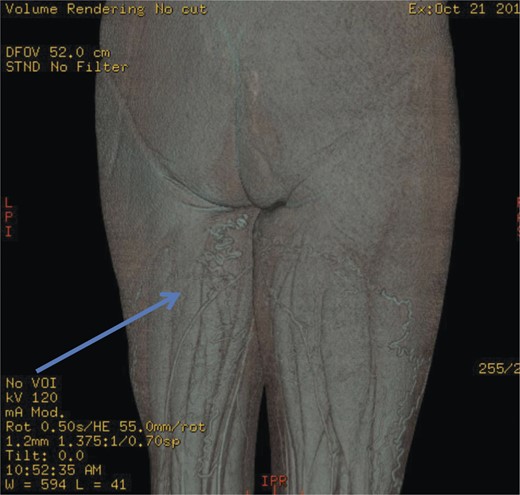

Computed pelvic venography showing communication of thigh veins to vulval varices (blue arrow).

The superficial external pudendal vein was embolized with 1% sodium tetradecyl sulphate and then coiled through a contralateral puncture under fluoroscopic guidance (Figs 3 and 4). The procedure went uneventfully with successful obliteration of the communicating thigh veins to vulval varices (Fig. 5) and the patient was discharged home the same day.

Pre-embolization fluoroscopy showing communication of thigh veins to vulval varices (blue arrow).